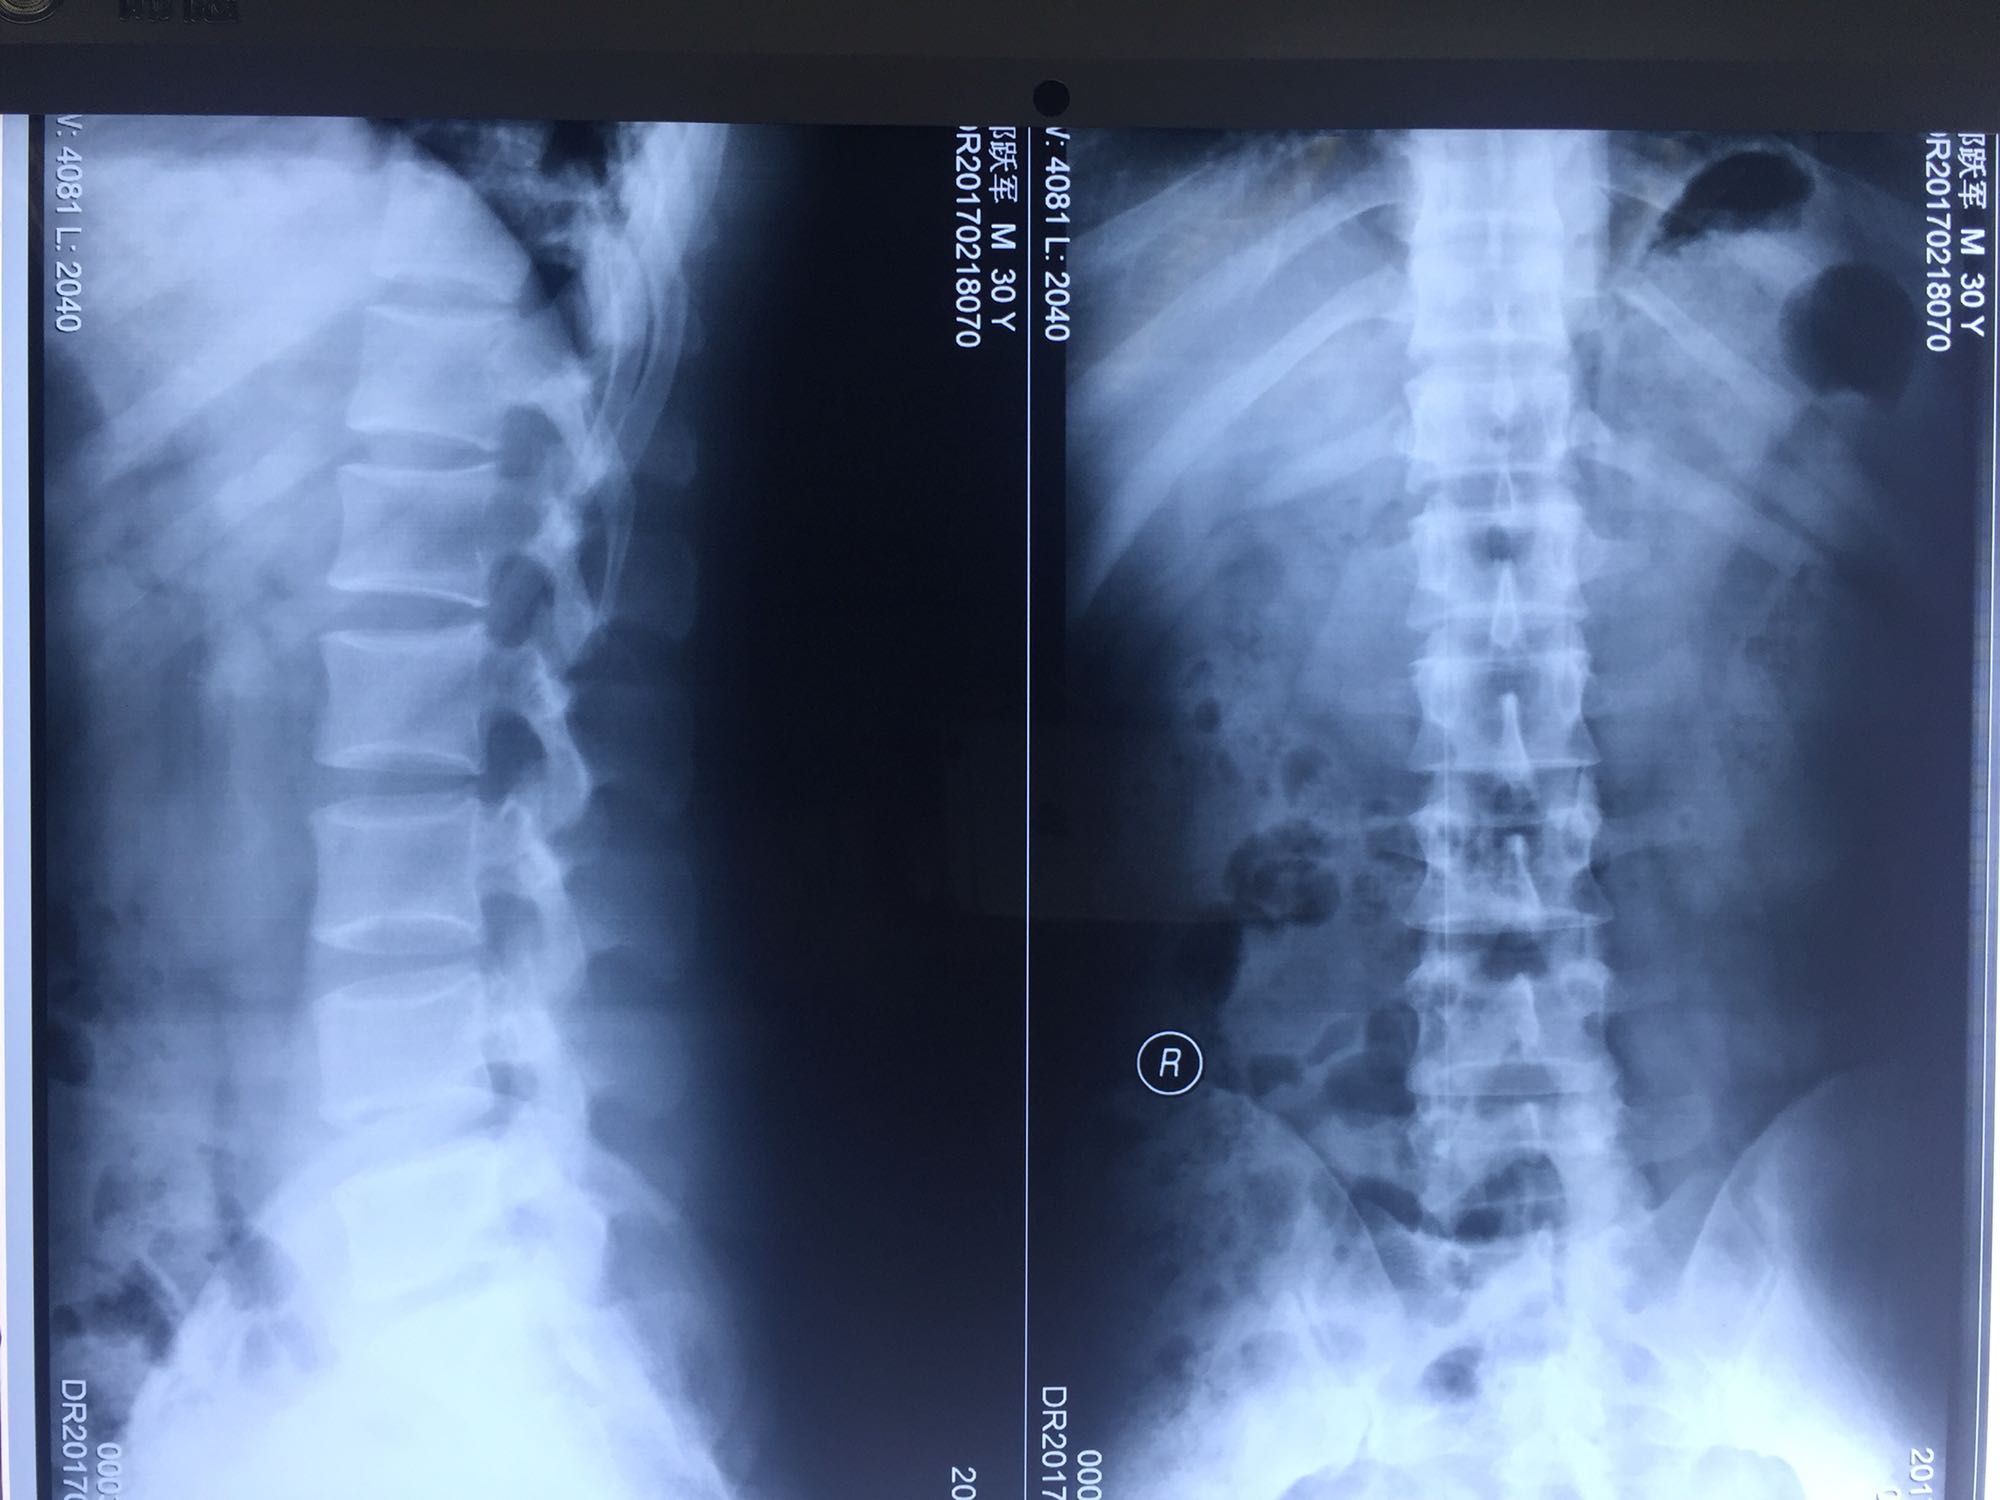

邝X军,男性,30岁,因左下肢疼痛1天而入院。 1天前无明显诱因出现左下肢疼痛,程度较重,难以忍受,伴有行走困难。

腰骶部肌紧张,腰5骶1棘间及左侧椎旁有压痛及放散痛,左侧坐骨神经出孔处有压痛及放散痛,左侧足背外侧及足底部皮肤感觉麻木,左侧直腿抬高试验阳性(30度)。

诊断:腰5骶1椎间盘突出症 治疗方案:椎间孔镜下经椎板间入路髓核摘除术